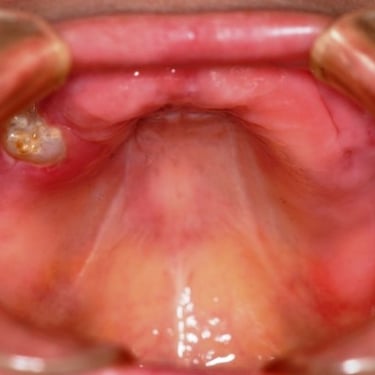

Edentulismo completo

El edentulismo completo es la ausencia total de dientes en una o ambas arcadas.

Los pacientes tienen dificultad para masticar, hablar y pueden sentirse incómodos con su apariencia.

El tratamiento puede incluir la colocación de una prótesis completa sobre implantes, proporcionando una solución fija y estable